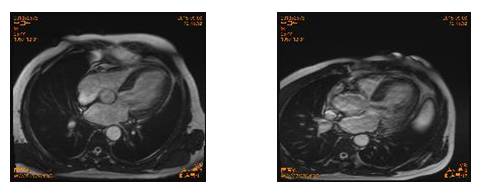

2015-9-13【心脏MR】

影像描述:左心增大(左房28cm2),室间隔略增厚,左室前壁、侧壁心尖段、心尖部室腔内见交错排列的肌小梁结构,厚度增加,肌小梁/左室壁厚度约为1.5。升主动脉根部直径约4.9cm。

左心功能测定:左室舒张末期容量175ml,左室收缩末期容量123ml,左室射血分数30%。

诊断意见:左室致密化不全,心功能下降,左心增大,主动脉瓣中度关闭不全,二尖瓣、三尖瓣轻度关闭不全,升主动脉增宽。

心脏MRI:

左室乳头肌水平至心尖部丰富网格状影